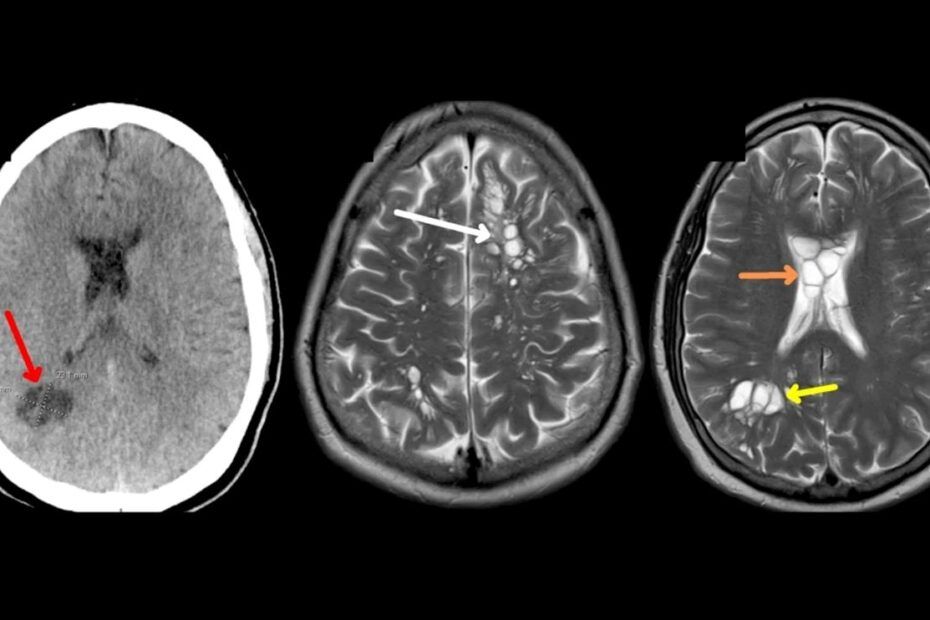

După internarea în spital pentru investigații suplimentare, scanările CT au arătat prezența mai multor chisturi umplute cu lichid în creier. Testele serologice pentru detectarea anticorpilor specifici cisticercozei au fost pozitive, confirmând diagnosticul de neurocisticercoză pentru pacient, așa cum este menționat în studiu. Neurocisticercoza este o infecție parazitară a țesuturilor cauzată de larvele chistice ale teniei de porc, localizate în creier, așa cum explică Centrele pentru Controlul și Prevenirea Bolilor (CDC).